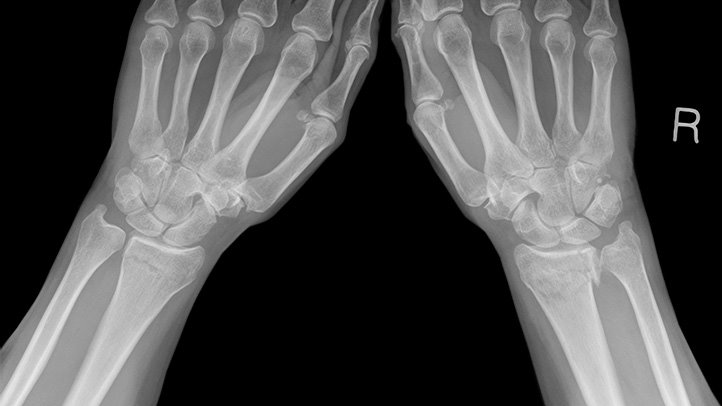

Tulang kaki x ray. Bahagian yang terlibat dalam pemeriksaan x ray lutut ialah lutut termasuk bahagian tulang lutut tulang paha tulang di atas lutut tibia dan fibula tulang kaki yang lebih rendah patela tempurung lutut dan tisu lembut. Penampakan x ray yang menunjukkan bahaya menaruh kaki di atas dashboard mobil twitter dpgosafeskipper pada dasarnya seluruh sisi kananku patah. Apa itu pemeriksaan x ray lutut. Jika pembedahan kaki akan dijalankan x ray kaki akan diambil terlebih dahulu untuk membantu perancangan dalam pembedahan dan juga akan diambil selepas pembedahan.

Pemeriksaan x ray kaki boleh membantu mencari punca punca dan tanda tanda seperti sakit ketegangan bengkak atau kecacatan kaki. Jika anda merasakan nyeri yang hebat dan tidak sembuh sembuh di bagian punggung anda akan diminta melakukan tindakan radiologi seperti x ray atau foto rontgen. Contoh traksi ini mungkin ada yang pernah melihatnya di film atau langsung di rs. Hasil x ray fraktur tibia fibula posisi ventro dorsal.

Di nilai kesegarisan antara tulang satu dengan yang lain pada persendian.